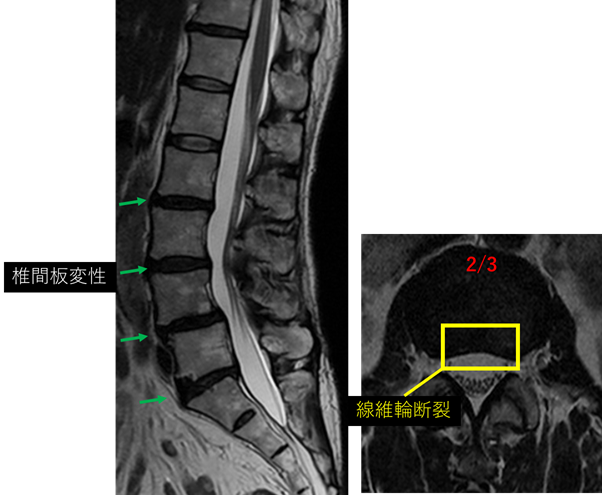

画像及び所見について

L1/2: 異常なし

L2/3: 変性、繊維輪断裂

L3/4: 変性、膨隆

L4/5: 変性、膨隆、終板変性(Modic2)

L5/S: 変性、膨隆、終板変性(Modic3)

以上の事が画像上認められます。

L2/3、3/4、4/5、5/S に

椎間板変性症、椎間板膨隆、繊維輪断裂、終板変性 を認め、主症状の原因の可能性が高い。